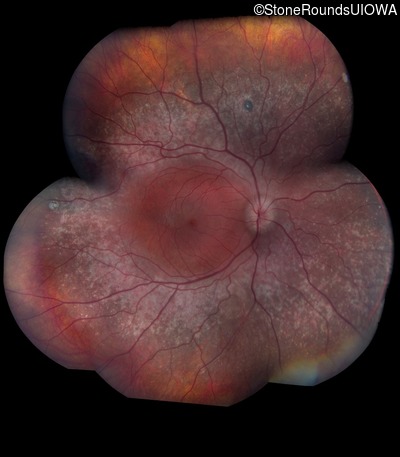

Age at visit: 18 years